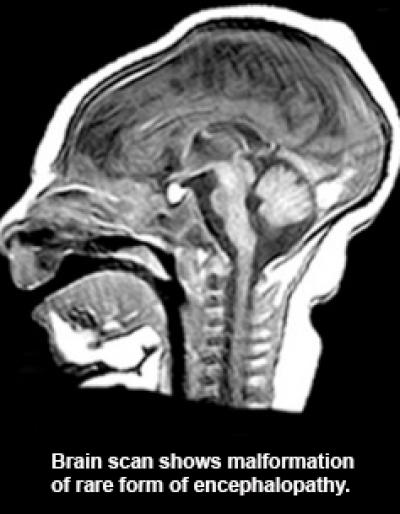

DURHAM, N.C. – Though worlds apart, four unrelated families have been united in a medical mystery over the source of a rare inherited disorder that results in their children being born with abnormal brain growth and severe functional impairments.

Goldstein said the work on the rare disorder was launched after two separate families in Israel, both of Iranian Jewish ancestry, had children with similar impairments – small head circumference that grows progressively worse, accompanied by profound developmental delays and seizures.